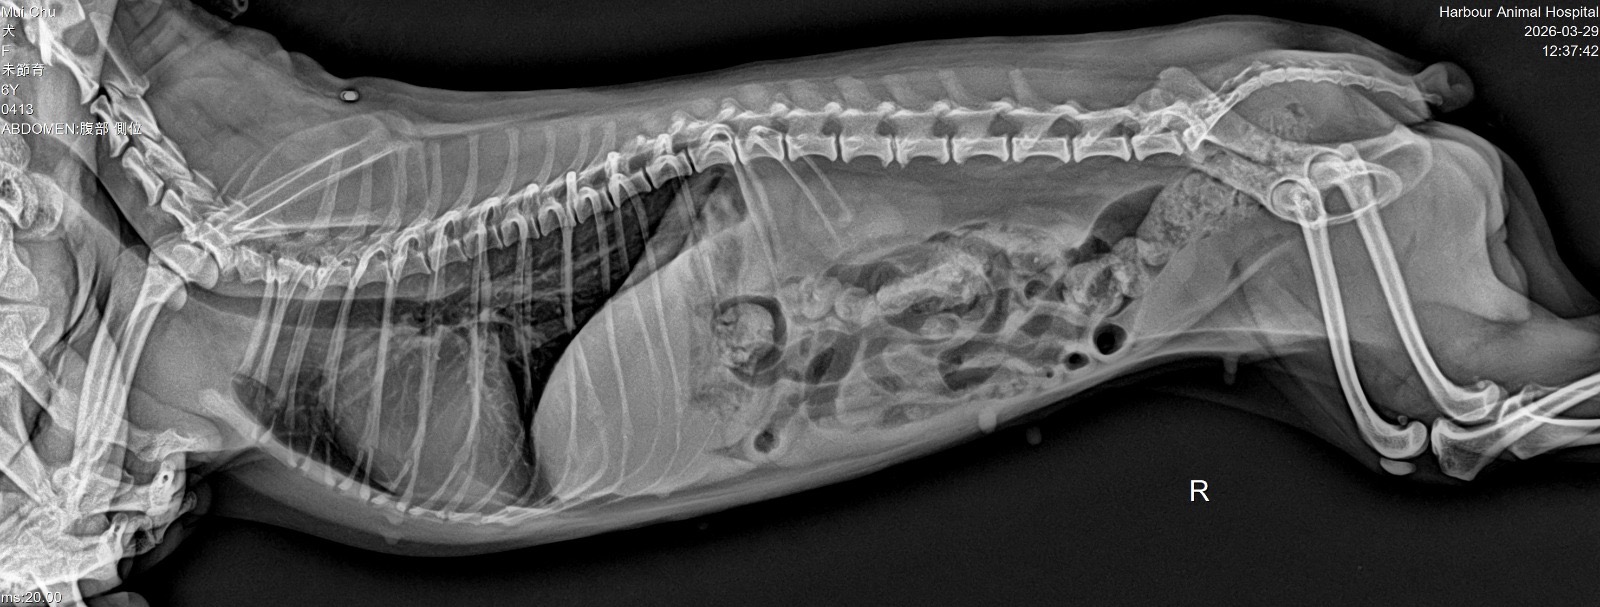

妹豬睇醫生 Get link Facebook X Pinterest Email Other Apps March 29, 2026 由於妹豬忍尿問題已有一段時日,星期六帶妹豬的尿去驗,夜間獲通知有晶石,所以星期日需帶妹豬去檢查!蔽日帶妹豬去診所照X光,萬幸無結石,只需食藥,但將來要留意骨刺的問題 Get link Facebook X Pinterest Email Other Apps Comments